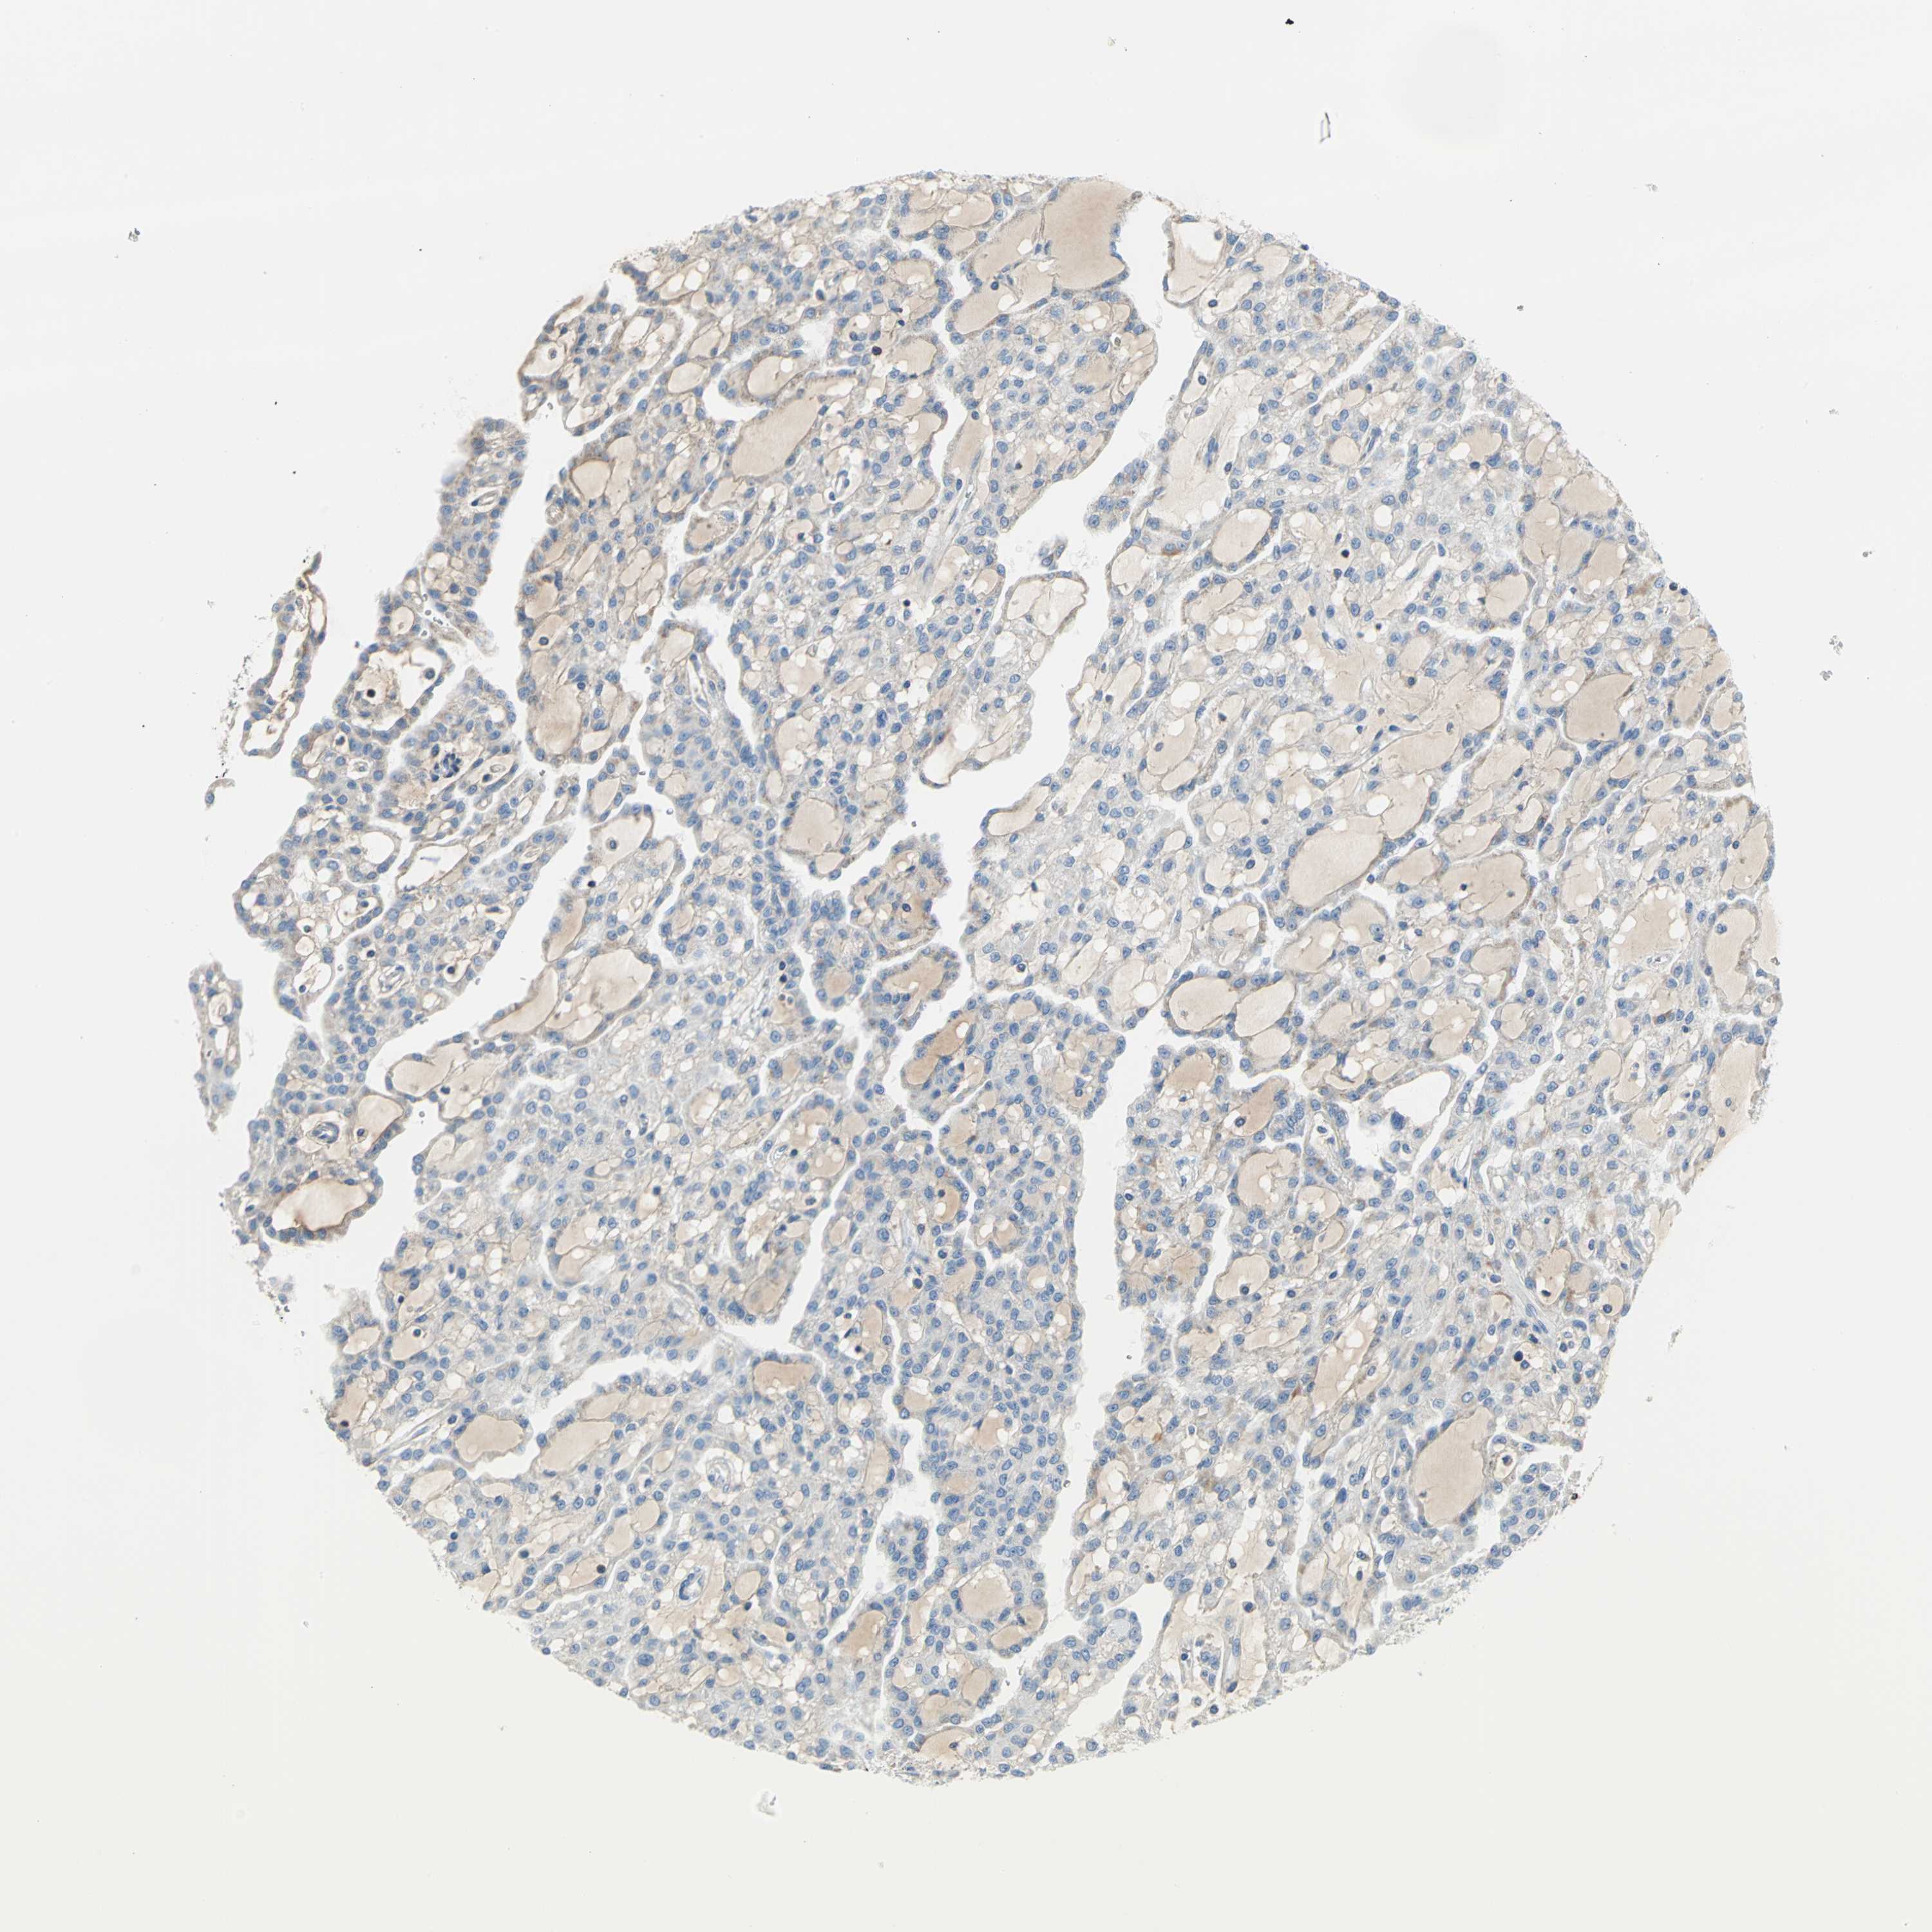

KIDNEY RENAL CLEAR CELL CARCINOMA (VALIDATION) - Interactive survival scatter ploti

The Survival Scatter plot shows the clinical status (i.e. dead or alive) for all individuals in the patient cohort, based on the same data that underlies the corresponding Kaplan-Meier plots. Patients that are alive at last time for follow-up are shown in blue and patients who have died during the study are shown in red.

The x-axis shows the expression levels (FPKM) of the investigated gene in the tumor tissue at the time of diagnosis. The y-axis shows the follow-up time after diagnosis (years). Both axes are complimented with kernel density curves demonstrating the data density over the axes. The top density plot shows the expression levels (FPKM) distribution among dead (red) and alive patients (blue). The right density plot shows the data density of the survived years of dead patients with high and low expression levels respectively, stratified using the cutoff indicated by the vertical dashed line through the Survival Scatter plot. This cutoff is automatically defined based on the FPKM cutoff that minimizes the p-score. The cutoff can be changed by dragging the vertical line or by entering a cutoff value in the square labeled "Current cut-off".

Under the Survival Scatter plot the p-score landscape (black curve; left axis) is shown together with dead median separation (red curve; right axis). Dead median separation is the difference in median mRNA expression between patients who have died with high and low expression, respectively. It is calculated as follows: median FPKM expression of dead patients with high expression - median FPKM expression of dead patients with low expression. This is intended to aid the user in visually exploring custom cutoffs and the associated p-scores and dead median separation.

Individual patient data is displayed and can be filtered by clicking on one or more of the category buttons on the top of the page. Categories describing expression level and patient information include: high, low, alive, dead, female, male and tumor stages. The scale of the x-axis can be toggled between linear and log-scale by clicking on the "x log" button. Mouse-over function shows TCGA ID, patient information and mRNA expression (FPKM) for each patient.

& Survival analysisi

Kaplan-Meier plots summarize results from analysis of correlation between mRNA expression level and patient survival. Patients were divided based on level of expression into one of the two groups "low" (under cut off) or "high" (over cut off). X-axis shows time for survival (years) and y-axis shows the probability of survival, where 1.0 corresponds to 100 percent.

ALOX15 is not prognostic in Kidney Renal Clear Cell Carcinoma (validation)

TCGA RNA samplesi

RNA-seq data is reported as average FPKM (number Fragments Per Kilobase of exon per Million reads), generated by the The Cancer Genome Atlas (TCGA) .

Normal distribution across the dataset is visualized with box plots, shown as median and 25th and 75th percentiles. Points are displayed as outliers if they are above or below 1.5 times the interquartile range. FPKM values of the individual samples are presented next to the box plot.

Average pTPM 0.0

Number of samples 100